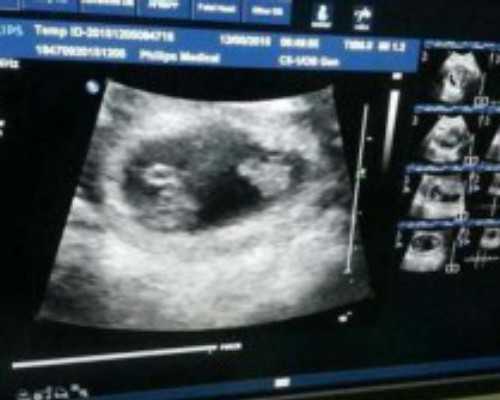

治疗方法:对于卵巢功能减退导致的卵泡发育问题,治疗方法可能包括激素替代治疗、促排卵治疗等。在某些情况下,还可以考虑试管婴儿等辅助生殖技术。此外,保持良好的生活习惯,如健康饮食、适量运动、减少吸烟和饮酒等,有助于维护卵巢功能。